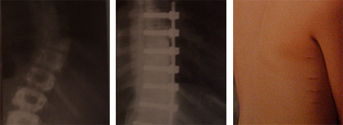

Técnicas 1

Fractura vertebral por estallido, inestable,

con un índice sagital (cifosis) no tolerable

Técnicas 2

Imagen de la fractura y del postoperatorio con una reducción anatómica

y una visión de la espalda de la paciente con incisiones puntiformes

a las 48 horas de la intervención, en el momento de recibir el alta.